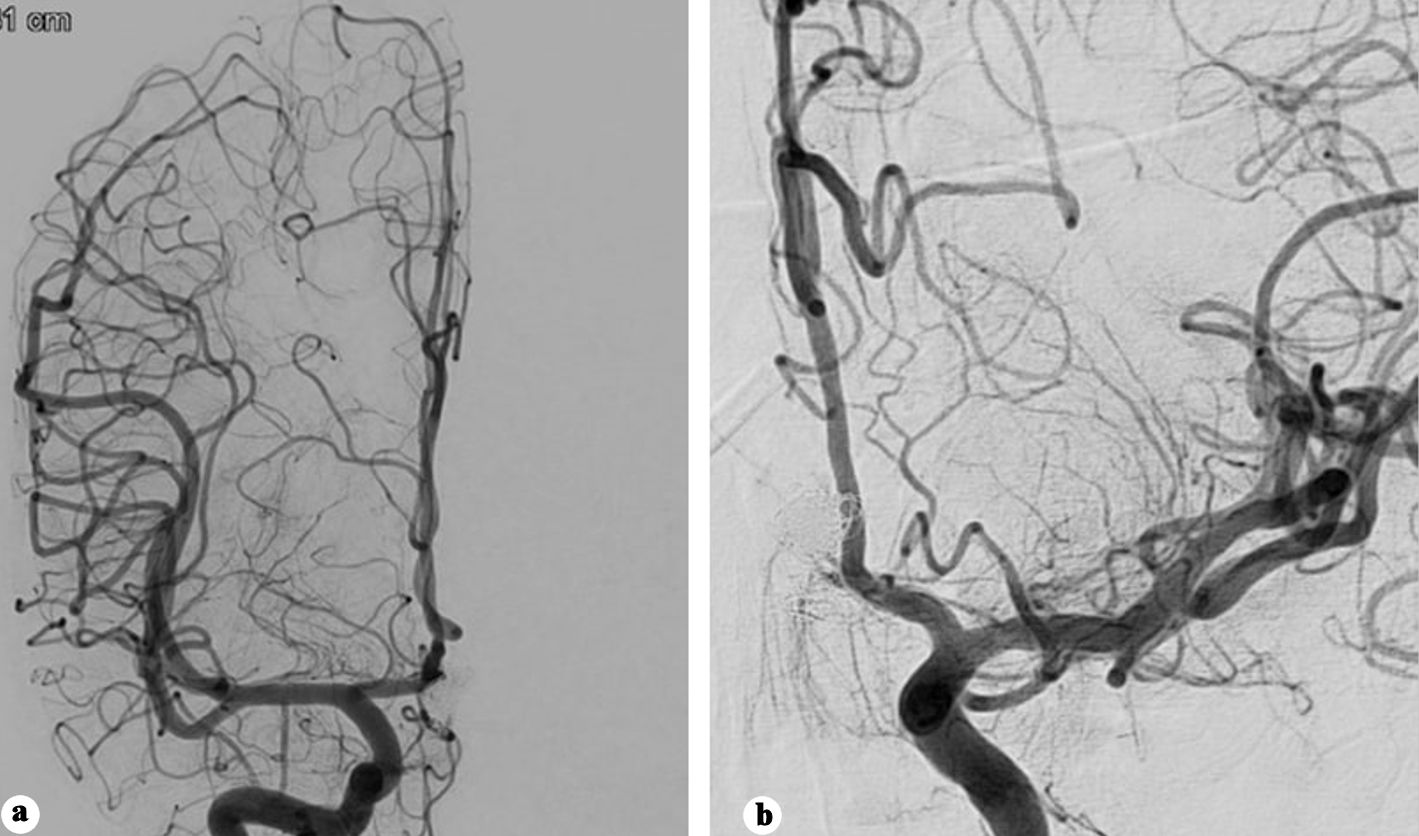

On day 10 post-coiling, the patient had another seizure episode along with decreased consciousness level (GCS 8). CT demonstrated significant rebleed with expansion of the interhemispheric hematoma reaching 38 mm in transverse axis, associated with intraventricular hemorrhage (Fig. 3a). Emergent 2D and 3D angiography identified an 8 mm pseudoaneurysm arising from the posterosuperior ACoA wall, while the coiled aneurysm was morphologically unchanged (Fig. 3b-c).

Figure 3. (a) Plain CT showing significant enlargement of the interhemispheric hematoma. (b) Anteroposterior view angiography showing developing of a pseudoaneurysm. (c) Three-dimensional (3D) angiography showing the development of a pseudoaneurysm opposite the previously coiled aneurysm. (d) Post-clipping subtracted angiography showing disappearance of the pseudoaneurysm. (e) Post-clipping native subtracted angiography showing disappearance of the pseudoaneurysm. CT: computed tomography.

The pseudoaneurysm was clipped via a left pterional craniotomy, and an external ventricular drain was inserted. Intraoperatively, the pseudoaneurysm was observed as a contained hematoma. Due to the absence of a clearly identifiable neck, the clip was applied as close as possible to the ACoA. Indocyanine green angiography confirmed aneurysm exclusion with preservation of the ACoA patency. Twenty-four hours later, a conventional angiography confirmed disappearance of the pseudoaneurysm (Fig. 3d, e).

Eight days after clipping, the patient developed sudden headaches associated with right-side hemiplegia. CT, CTA, and CT perfusion showed a bifrontal parasagittal perfusion defect and recurrence of the clipped pseudoaneurysm (Fig. 4a), which was immediately treated with coiling under protection of balloon remodeling, and intra-arterial vasodilator infusion (Fig. 4b, c).

Figure 4. (a) CTA showing recurrence of the pseudo sac post clipping. (b) Native angiography showing recanalization of the pseudoaneurysm. (c) Subtracted angiography post coiling of the pseudoaneurysm. (d) Subtracted angiography showing early recanalization of the pseudoaneurysm base. (e) Native acquisition showing the flow diverter deployed in the left side. CT: computed tomography.

One week later, the GCS improved to 13, and he regained full motor recovery. Follow-up angiography 9 days post-coiling revealed early recanalization at the pseudoaneurysm base (Fig. 4d). Ticagrelor 180 mg, acetylsalicylic acid 300 mg were initiated as a loading dose, and a Silk Vista Baby flow diverter (Balt Extrusion, Montmorency, France) was deployed extending from the left A2 to left A1segment (Fig. 4e), covering the irregularity previously noticed in the left A1 segment. Dual antiplatelet regimen (90 mg ticagrelor twice daily (BID) and 100 mg acetylsalicylic acid) was continued for 10 months.

Following a 6-week hospital stay, the patient was discharged in a fully conscious state with no residual deficits. The 10-month follow-up angiography demonstrated a patent flow diverter without evidence of intimal hyperplasia and no residual aneurysm filling (Fig. 5a, b).

Figure 5. (a) Anteroposterior view of right internal carotid angiography showing no filling of the aneurysm. (b) Anteroposterior view of left internal carotid angiography showing no filling of the aneurysm.